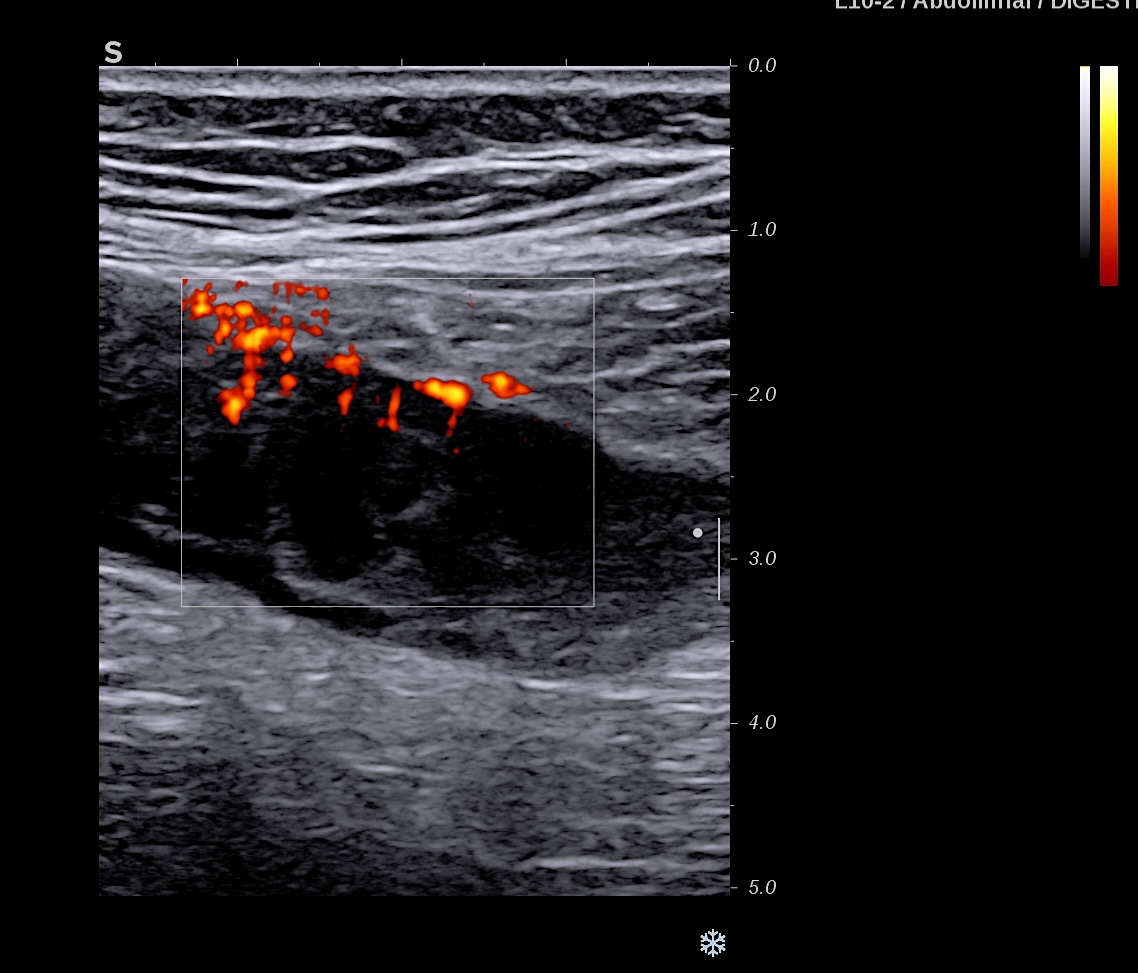

Activité Doppler intense de la paroi et de la graisse

Maladie de Crohn intense activité Doppler paroi et graisse